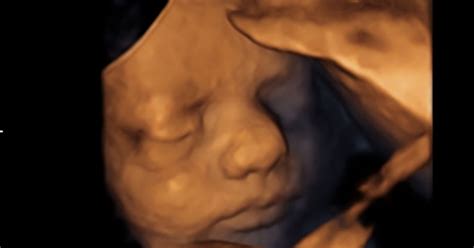

Naravni porod omogoča otroku, da plodovnico učinkovito iztisne iz pljuč, kar mu pomaga lažje in lepše zadihati ob rojstvu. Nekateri znanstveniki celo sumijo, da imajo otroci, rojeni s carskim rezom, višje tveganje za razvoj avtoimunskih bolezni.